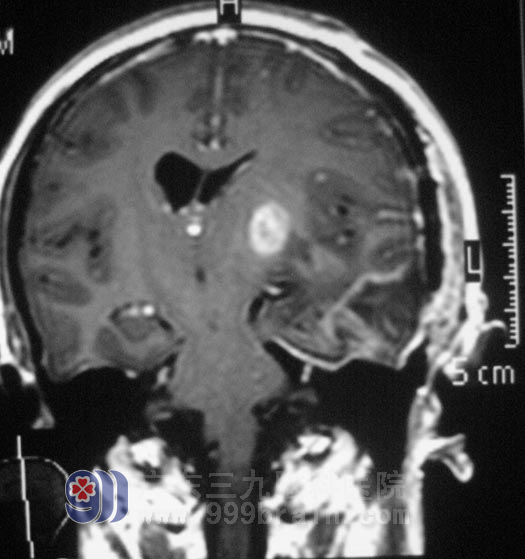

唐女士今年42岁,近半个月时间经常感觉头痛。以为是神经衰弱,脑供血不足,颈椎有问题,服用安神补脑液、颈复康等药物,没有做过检查。两天前无明显诱因出现头痛伴右侧肢体麻木,当地医院CT检查提示“左侧基底节区占位,考虑恶性肿瘤”。在广州某大医院头颅MR证实为:左侧基底节区占位,考虑恶性肿瘤。http://www.999brain.com/

广东三九脑科医院综合神经外科 鲁明主任结合唐女士的病史和影像资料,初步判断为星形细胞瘤:

7月27日,由鲁明主任主刀,在全麻下行左侧基底节区肿瘤切除+左侧颞叶部分切除内减压术,使用导航仪定位,切开后见肿瘤呈灰白色烂鱼肉样,边界不清,在显微镜下切除基底节区外侧及前侧肿瘤,后侧肿瘤部分切除,左侧颞叶颞极脑组织水肿厉害,予部分颞叶切除,缓解颅内压力。手术过程顺利。术后予专科监护,唐女士顺利度过水肿期和出血期,感觉和肢体活动功能无异常,视物正常。病理证实为: 间变性星形细胞瘤 III级。入放疗科进一步治疗。